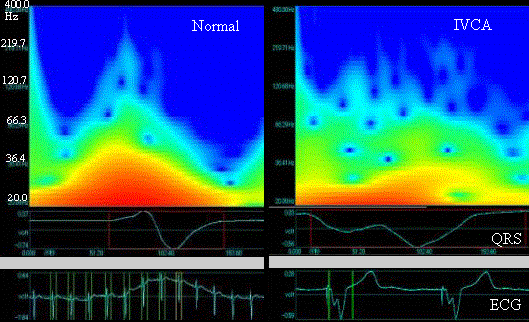

Figure 1. An representative cases of time-frequency relationships by use of wavelet transform. the vertical axis indicates the frequency, and the transverse one the time from the onset of QRS, surrounded by red frames. The color and its brightness show the magneitude of frequency power which is greater in red and smaller in green.

Two representative examples of frequency analysis of QRS in V3 are illustrated in figure 1. A normal case is shown in the left panel, where greater power, indicated by red zone, was observed at frequency range from 20 to 80Hz. The red zone was surrounded by middle frequency power (green zone). A case with abnormal QRS under right ventricular pacing was illustrated in the right panel. In this case, the red zone is narrower, and the green zone was distributed over wide range QRS interval. Moreover there are irregular upward projections of the light blue zone, denoting smaller power. The time integral of the power spectrum against the frequency were shown in figure 2. As seen in the left panel, the time integral was larger at low frequency (100Hz or less) with exponential decay at increasing frequencies in normal case (N). In IVCA, the integral values were smaller in low frequency range compared with those in normal cases. In IVCA with MI, the integral values were greater in high frequency range (150-250Hz), as indicated by an arrow in the right panel of figure 2, values from IVCA (ventricular paced beat) was smaller in low frequency range than it in normal. In contrast, the integral values from IVCA (CLBBB) plus MI was greater in high frequency range (200-250Hz), indicated by the arrow in right panel of figure 2. In addition, the number of sigma peak was larger in IVCA with MI was significantly larger than that in IVCA without MI (15.4±3.1 vs. 8.6±2.3).